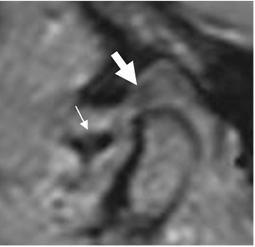

En estados crónicos de lesión del disco, puede encontrarse perforación o ruptura. (Fig 13 A y B).

Fig 13 A. Ruptura del disco.

RM sagital oblicua en GE. Ruptura de la zona intermedia, con desplazamiento y separación de la BA (Flecha delgada) y la BP (Flecha gruesa), la cual presenta cambios degenerativos.

Fig 13 B. Ruptura del disco.

RM sagital en GE. Cambios degenerativos en el cóndilo mandibular, con irregularidad y formación de osteofito anterior. Existe degeneración y ruptura del disco con separación de la banda anterior (Flecha delgada) y posterior. (Flecha gruesa).